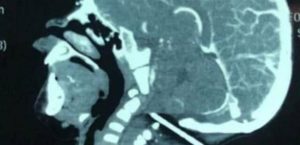

رضيع ينجو بأعجوبة من قضيب حديدي اخترق جمجمته

كان رضيع يبلغ من العمر عاما واحدا يلهو في في ساحة منزله عندما انزلق فجأة، ولسوء حظه وقع على قضيب … Continue reading رضيع ينجو بأعجوبة من قضيب حديدي اخترق جمجمته